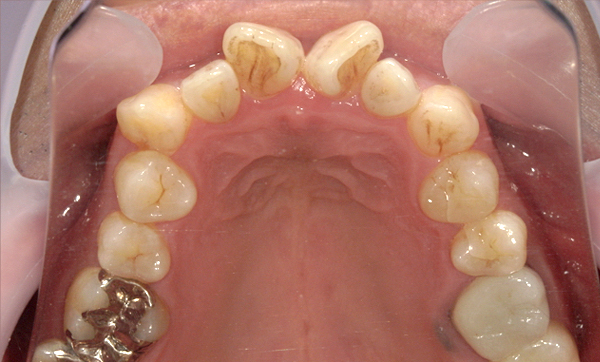

症例_013 前歯「八の字/V字型」症例

治療期間:8ヶ月金額:30万円+税20代女性八の字/V字型捻転歯上の前歯だけ